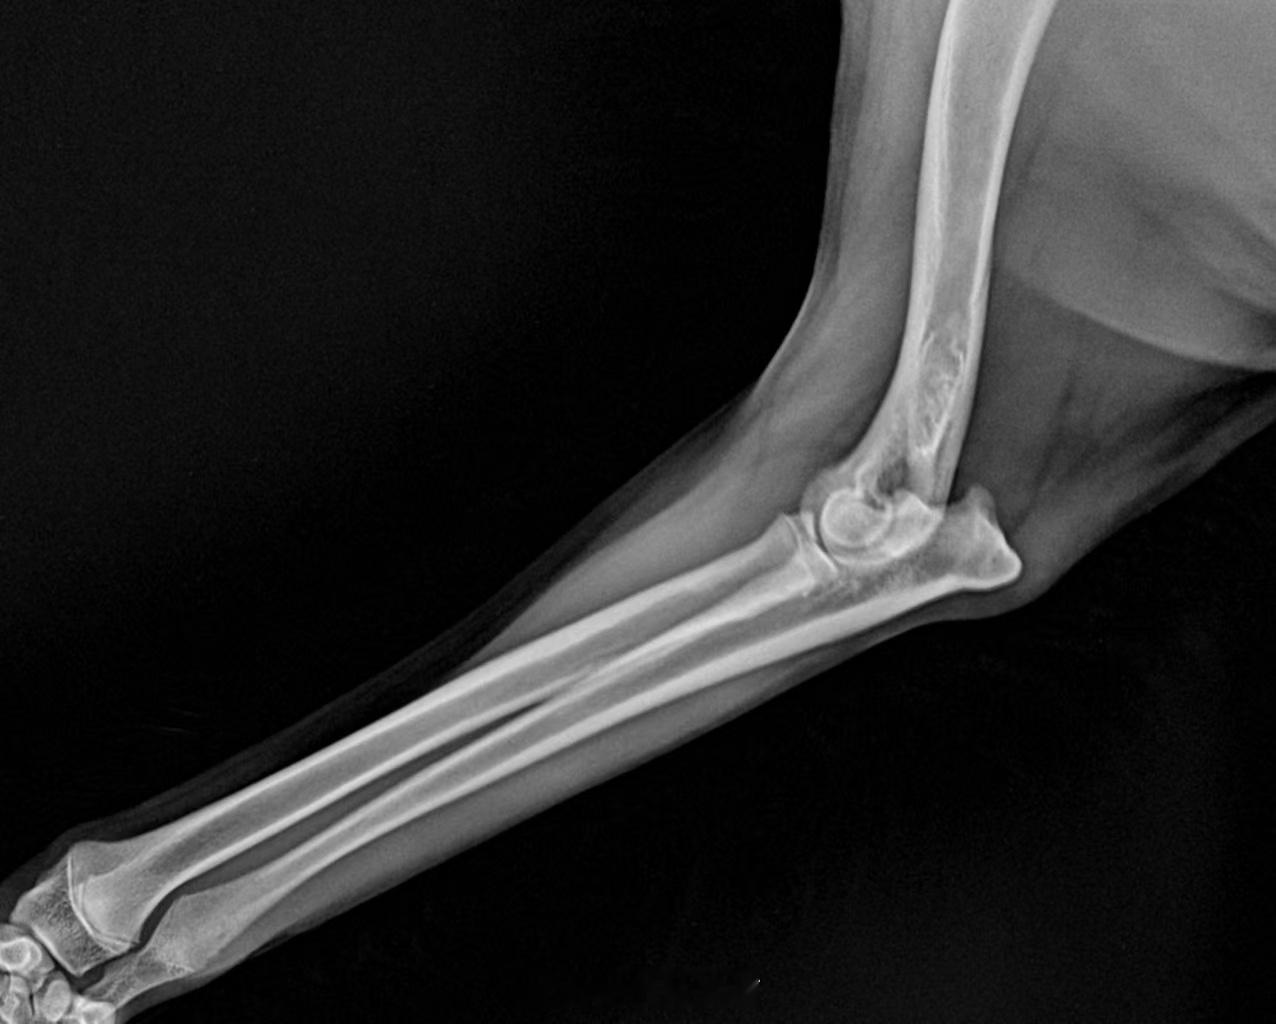

轻度生长痛,没有骨炎。